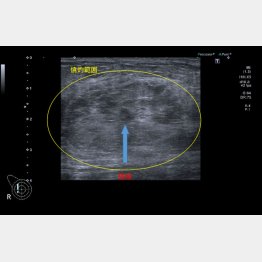

新たな治療選択肢とは「ラジオ波焼灼療法」だ。乳がんの中に細い電極針を差し込み、ラジオ波という電流を流して、がん細胞を死滅させる。肝臓がん、肺がん、悪性骨腫瘍などで保険適用となっていたが、2023年12月、乳がんも保険適用となった。